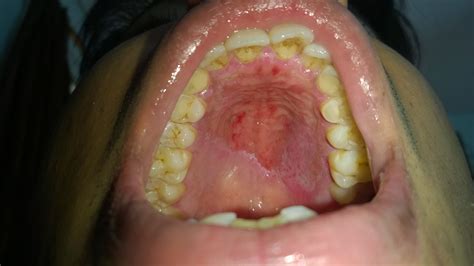

Can Vaping Cause Mouth Sores - EMSEKFLOL.COM